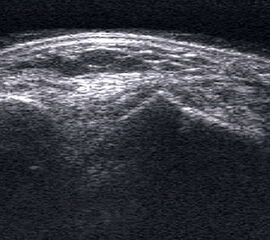

Ruptur Lig. fibulocalcaneare

Längsschnitt über dem Lig. fibulocalcaneare. Die Peronealsehnen erscheinen als echoreiche runde bis ovaläre Struktur.

Abbildung 19

Lagerung: Rückenlage, OSG in Neutralstellung.

Schnittebene: LS über Lig. fibulocalcaneare.

Referenzstrukturen: Fibulaspitze und Talus.

Befunde: Das Lig. fibulocalcaneare is nativ schlecht abgrenzbar, da es in die Tiefe und nicht parallel zum Schallkopf verläuft. Direkt über das Band ziehen quer getroffen die Peronäussehnen. Durch die Distorsion kann auch das Peritendineum peroneale einreißen. Die Peronealsehnen sind dann in ihrer Sehnenscheide von Blut umgeben, was sich als echoarmer Ring (Halo-Phänomen) darstellt und ein indirektes Zeichen für eine Verletzung des Lig. fibulocalcaneare ist.